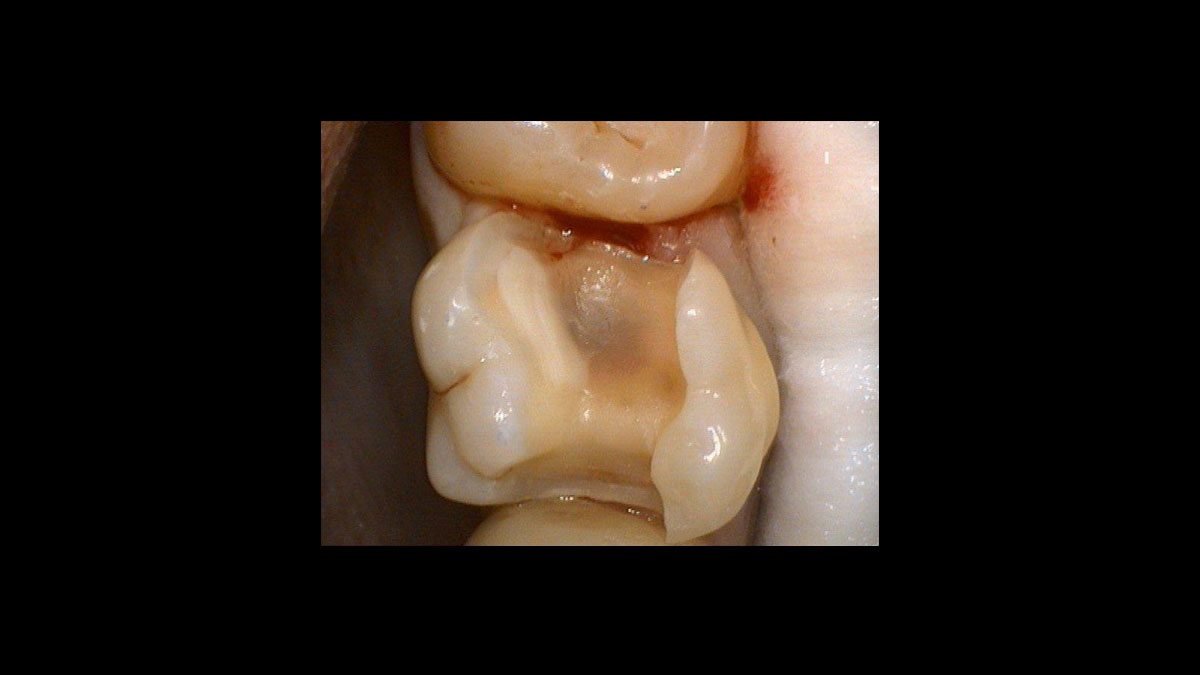

Endodontics

The following applications are presented in the videos and images:

• Endodontic germ reduction

• Gangrene germ reduction

Endodontic germ reduction